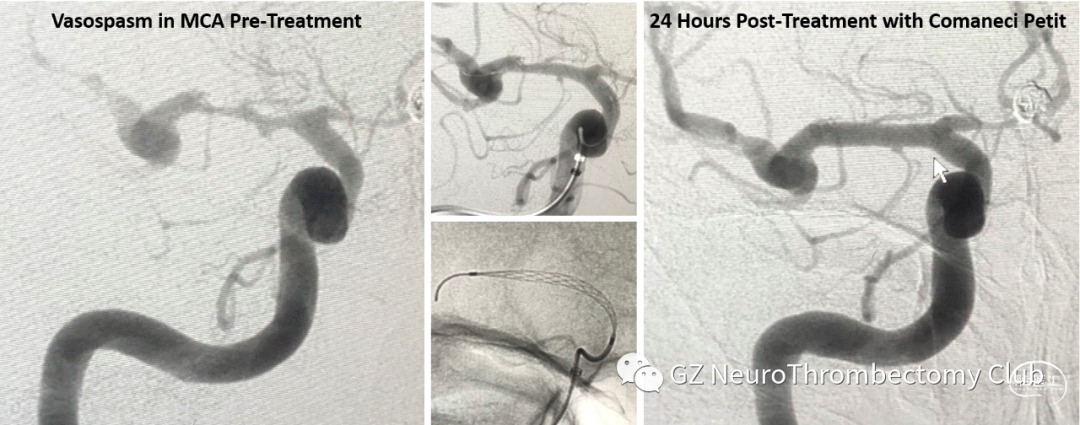

除了主打的辅助栓塞动脉瘤功能之外,Comaneci™ device 又开发出了新用途——治疗SAH导致的血管痉挛,而且还通过了FDA认证。

采用Comaneci™临时推挤机械扩张来改善血管痉挛,在以往动脉注射药物(血管扩张剂)和球囊扩张之间,找到了一种高效且安全的方式。